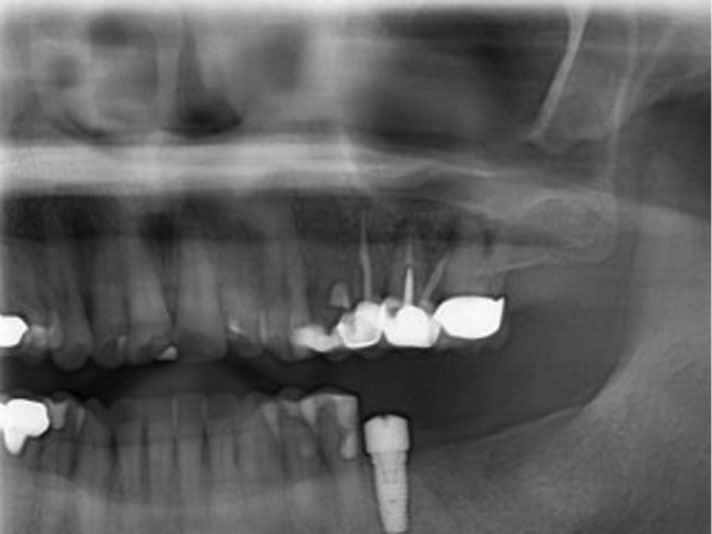

dental implant xray